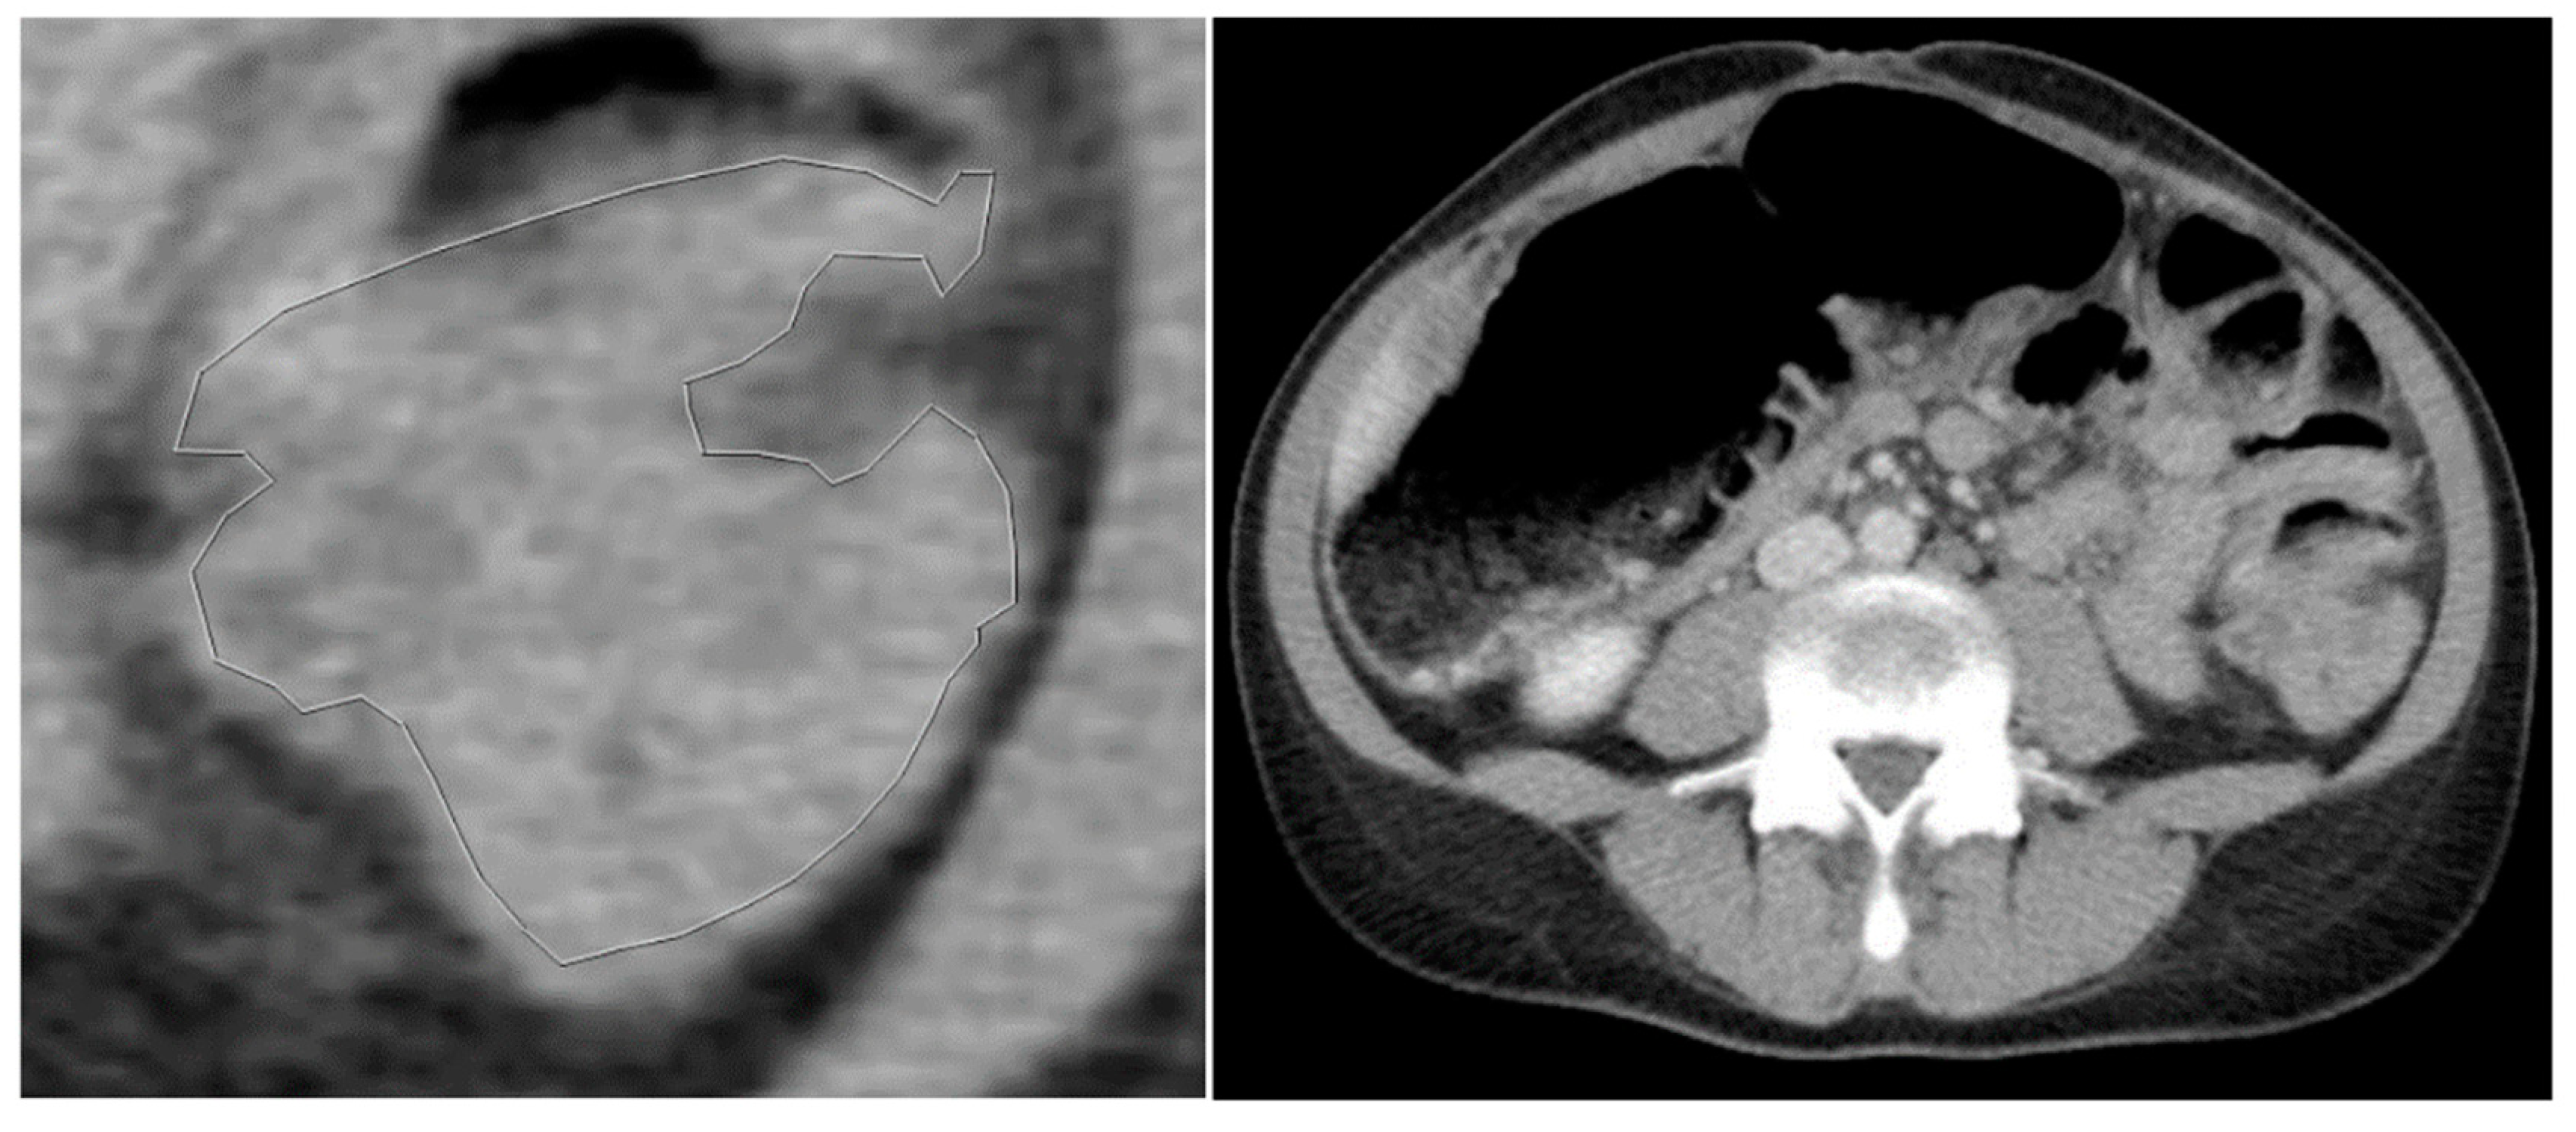

Figure 2. 58-year-old patient with KRAS mutated CRC. a) Tumour without any segmentation. b) Tumour manually segmented by an expert abdominal radiologist.

Figure 3. a) Manually segmented non-mutated KRAS tumour. b) Abdominal contrast-enhancement CT of the same patient.